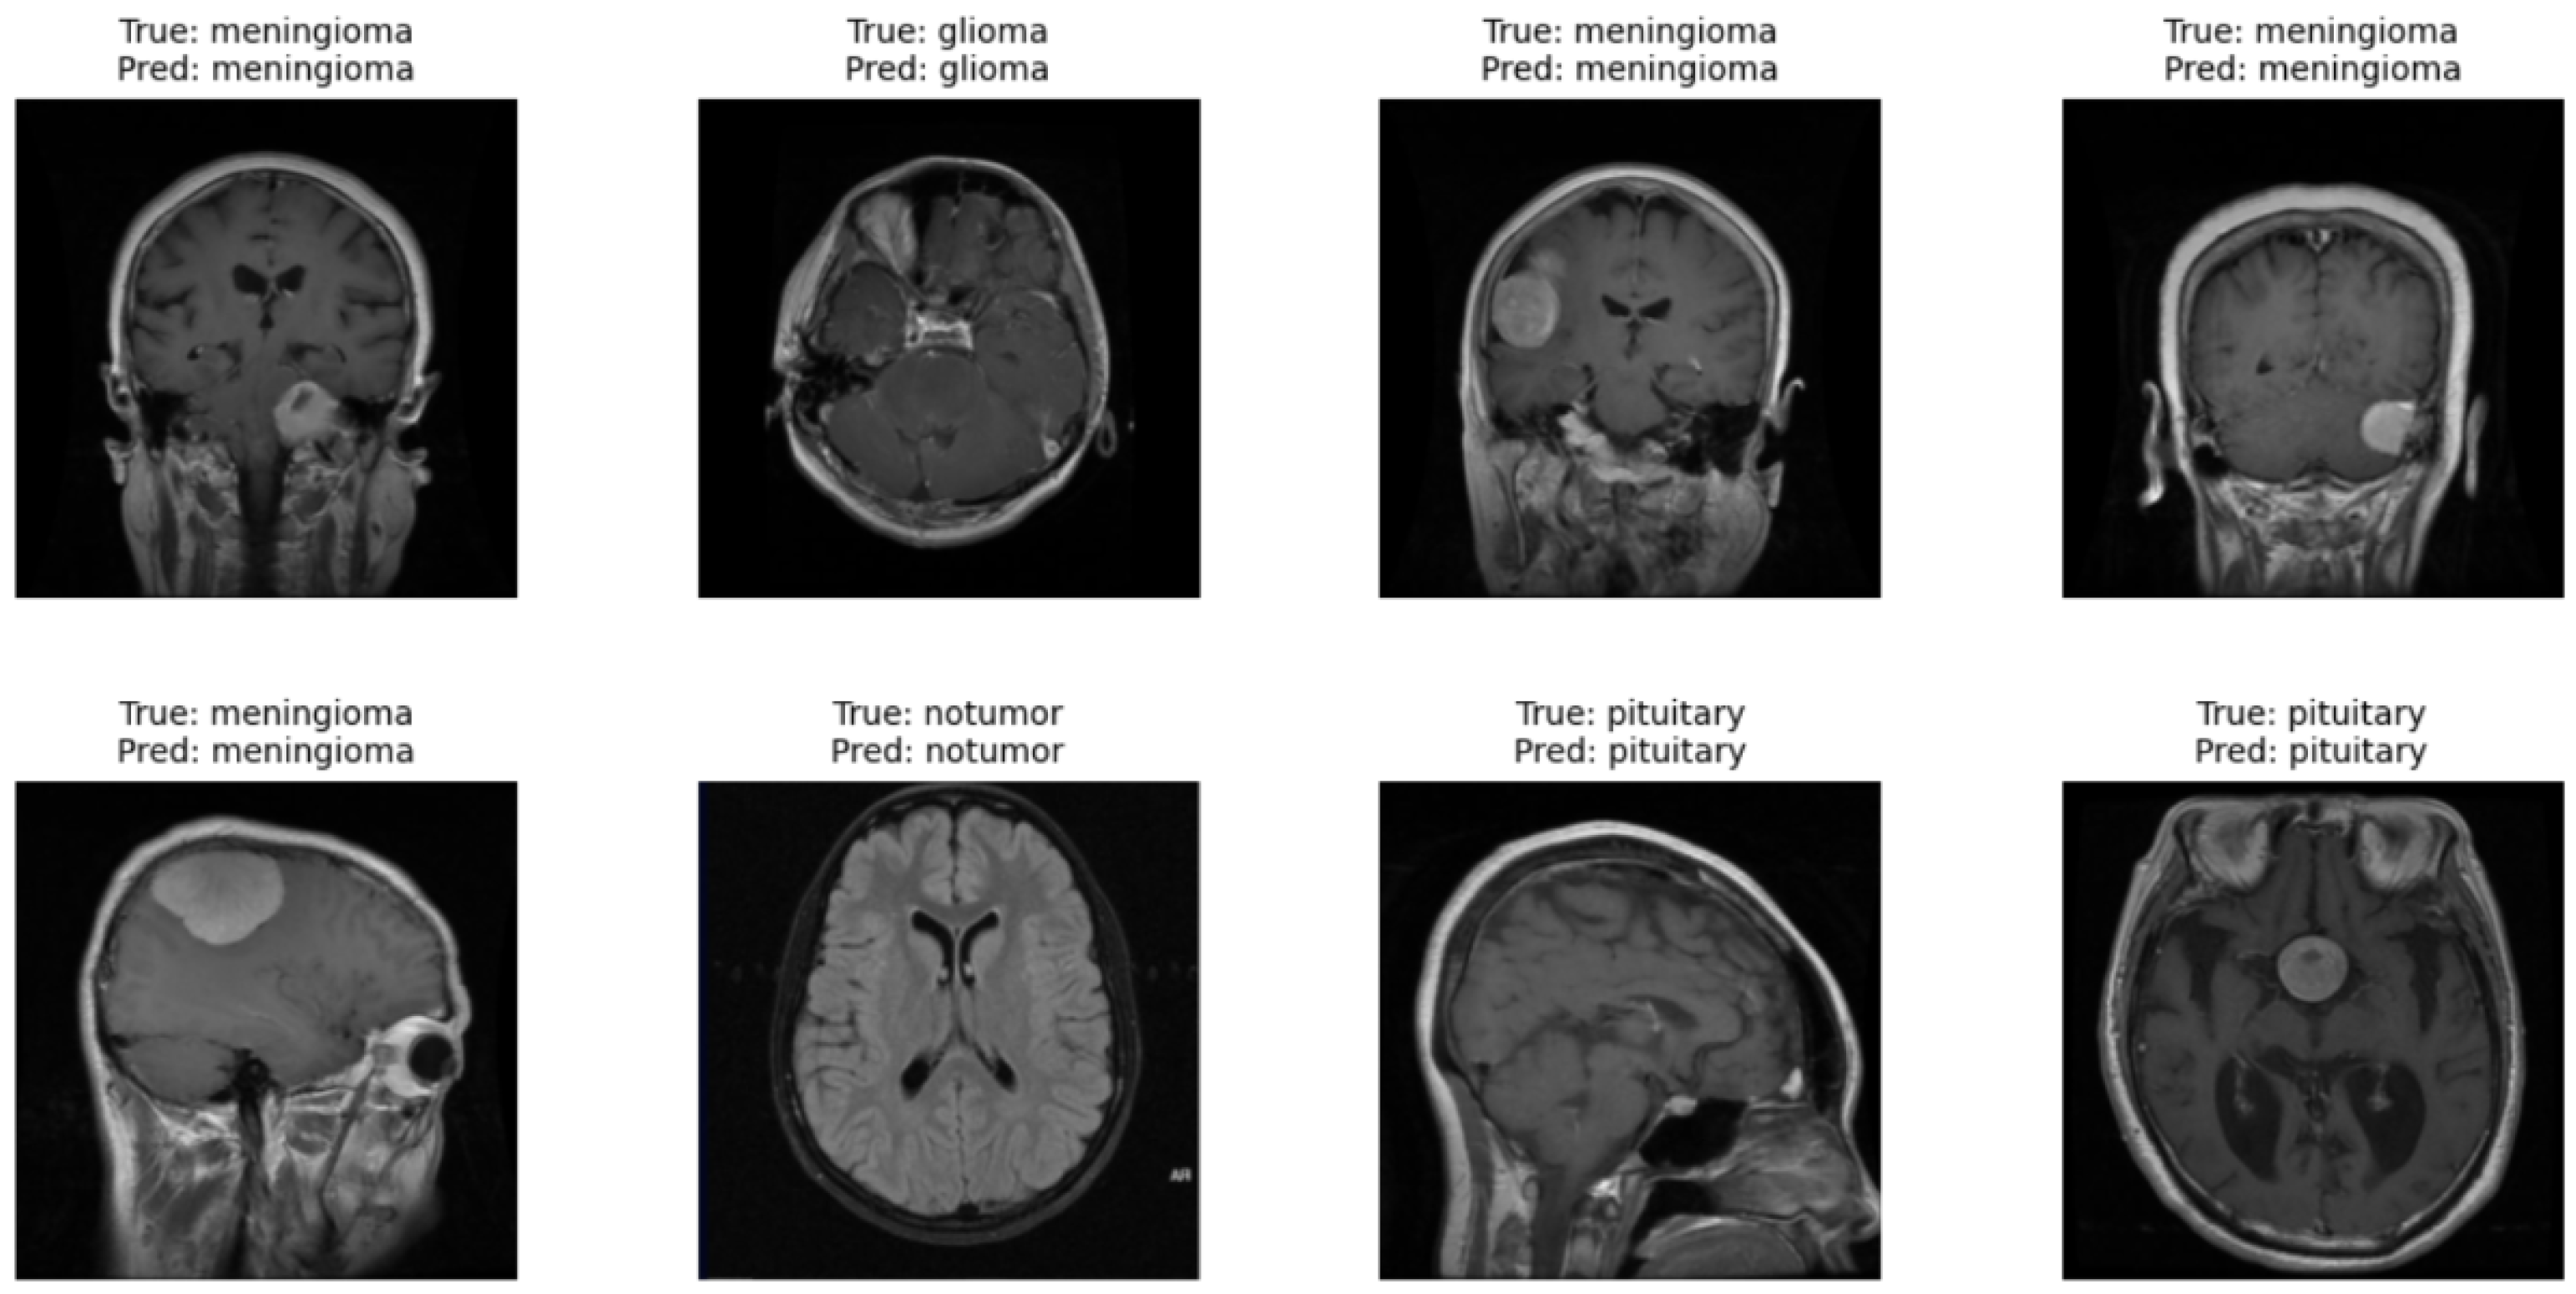

5.4. Vision Transformer

Figure 11 presents the results obtained with the Vision Transformer model applied to the test dataset. In each brain MRI image, it is possible to observe the indication of the true label (True) and the prediction of the model (Pred). The same figure shows correctly classified cases across all categories, where the model was able to identify both images of brains without tumors (no tumor) and different types of brain tumors, such as glioma, meningioma, and pituitary. This qualitative result demonstrates the ability of the ViT model to distinguish complex visual patterns in images, even when the differences between classes may be subtle. These observations complement the quantitative metrics obtained during model evaluation. The results show that the model can generalize effectively and correctly identify different conditions present in the images. Thus, qualitative analysis supports the quantitative results, reinforcing the robustness of the ViT model in the task of classifying brain tumors in magnetic resonance imaging.

Figure 11.

Qualitative results of the Vision Transformer model.